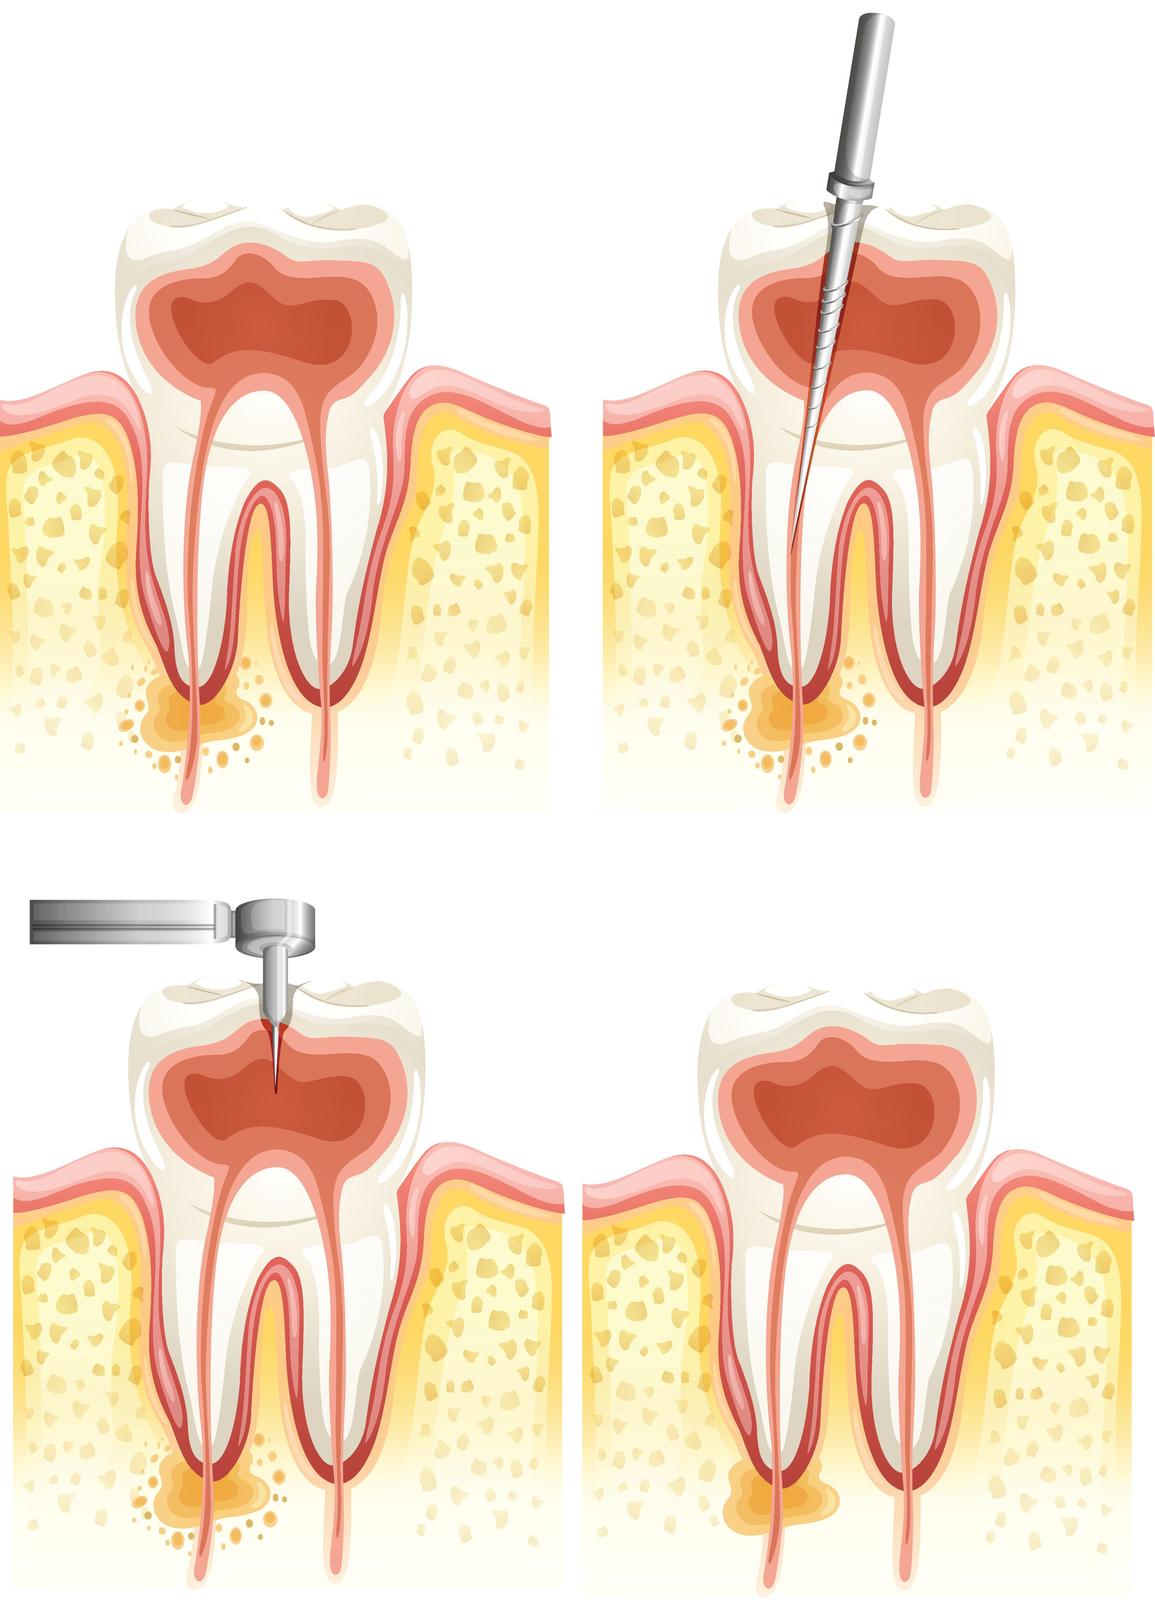

Reasons for this include a root that is still infected. It is foreseeable that although the root canal has been cleaned, it is found that some infections still remain inside. It can be that the filling or the crown has been built up too high and the directly opposite tooth comes down first before any of the of the teeth. This can irritate the tooth and can cause pain. You can still have infection remaining in the bone which is immediately around the apex of your tooth.

Dentists use the chemical sodium hydrochloride to disinfect the root canal. However if too much is used, it can leak out past the root and cause severe irritation. A common reason for pain after root canal treatment is when part of the root canal has been left behind without being fully disinfected. This infection gets worse and then causes pain. During the filling of the root canal it can happen that the material used to seal extrudes into the jaw bone. This causes irritation and pain.